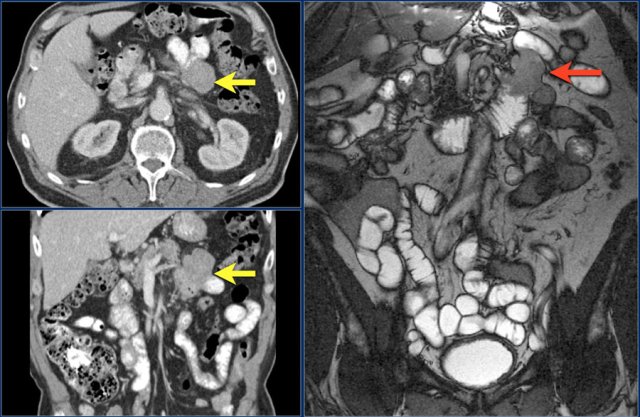

The findings are:

- Reversed fold pattern indicating celiac disease

- Ileal-ileal intussusception (yellow arrow), in a patient with multifocal small bowel lymphoma (not all lesions shown here).

- Mesenteric lymphadenopathy (red arrows).